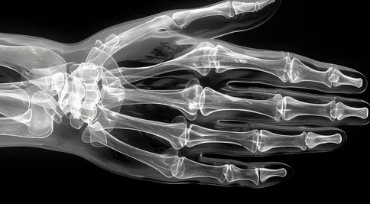

손가락 통증, 더 이상 참지 마세요! 원인, 증상, 치료 방법, 영양제, 운동 총정리

손가락 통증은 일상생활에 큰 불편을 초래하는 흔한 증상입니다. 단순한 근육통부터 관절염, 신경 손상 등 다양한 원인으로 발생할 수 있으며, 방치하면 만성 통증으로 이어질 수 있습니다. 손가락 통증의 원인과 증상을 정확히 파악하고, 적절한 치료 방법과 운동, 영양제 섭취를 통해 건강한 손을 되찾아 봅시다.